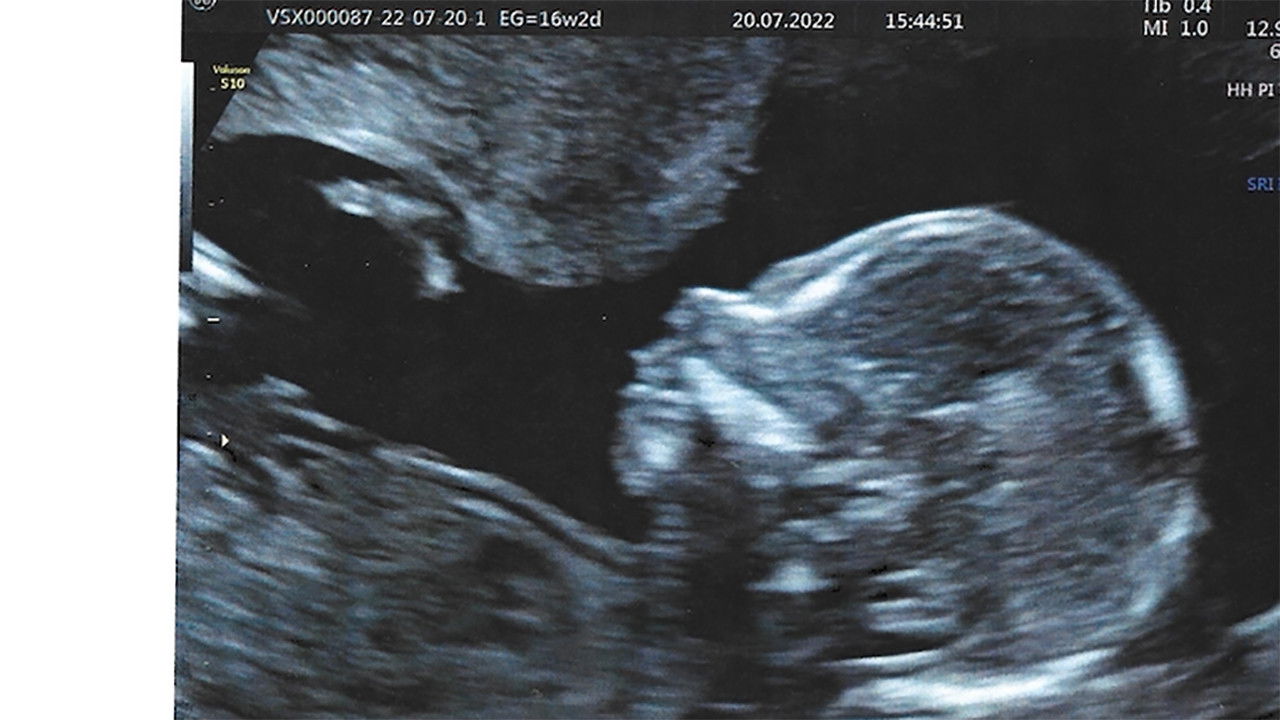

An acid humor essay that questions everyday aspects of life that make us need to achieve motherhood, with a critical view on contemporary maternity. Are we obsessed with what is biological? Is the cycle of mothers to daughters perpetuated?